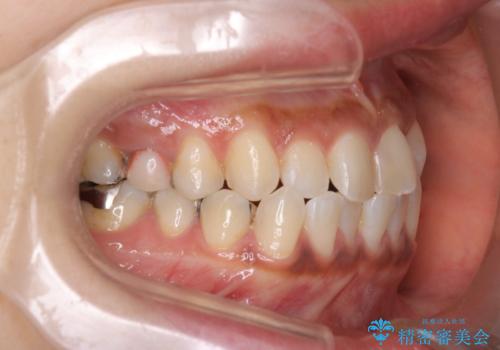

【インビザライン】前歯の凸凹をなおしたい

- 前歯の凸凹を主訴に来院されました。

インビザライン にて治療を行い、歯並びの改善を行うことができました。